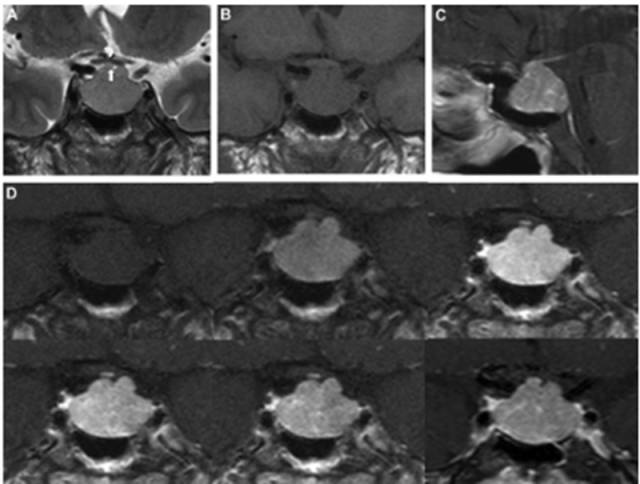

病例:男性,30岁,头痛2月

病理结果:富于淋巴浆细胞型脑膜瘤,WHO I级

2、CT密度较高,钙化少见。MR T1信号等或稍低、T2信号稍低或稍高,增强后呈明显强化;病灶内或边缘可见T1低信号、T2高信号区,增强后不强化;病灶边缘可见广泛增厚的脑膜强化。肿瘤界限模糊,似炎症,累及皮层,瘤周水肿明显(特征性表现)。

3、此亚型脑膜瘤有丰富的慢性炎细胞浸润,易伴发造血组织异常。病理上以上皮细胞增生伴大量淋巴细胞、浆细胞浸润为特点。